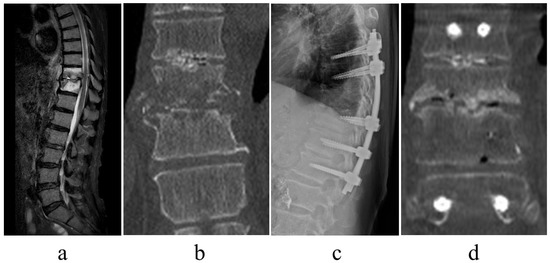

- Infection control. With minimally invasive posterior fixation and sensitive antibiotics, the inflammatory response normalized at an average of 42.8 days postoperatively. Previous reports stated that the period of normalization of the C-reactive protein concentration ranged from <1 month to 3 months; however, it was 42.8 days in this series [5,16]. In numerous patients, infection control was achieved without requiring additional surgery, thus implying that this technique is useful for infection control.

- Early ambulation. Less invasive procedures and pain reduction aid early ambulation. Herein, surgery significantly reduced pain (NRS for preoperative lower back pain was 5.9, which improved to 3.6 at the postoperative period of ambulation) and induced early ambulation (patients were able to ambulate at an average of 2.7 days postoperatively). For pain relief and time to ambulation, the results were comparable with those of previous studies [17,18]. Even in older patients, the minimally invasive procedure may enable early ambulation.

- Alignment maintenance. Local kyphosis, which is exacerbated by the destruction of the disk or vertebral body due to infection, is a measure of alignment maintenance. Minimally invasive posterior fixation improved local kyphosis by 6.6 degrees, with a postoperative correction loss of 3.6 degrees, which is comparable with results reported in previous studies (range: 3.4–6.8 degrees) [11,15,16]. These findings suggest that the range of fixation and fixation strength in this series were sufficient to maintain local alignment.